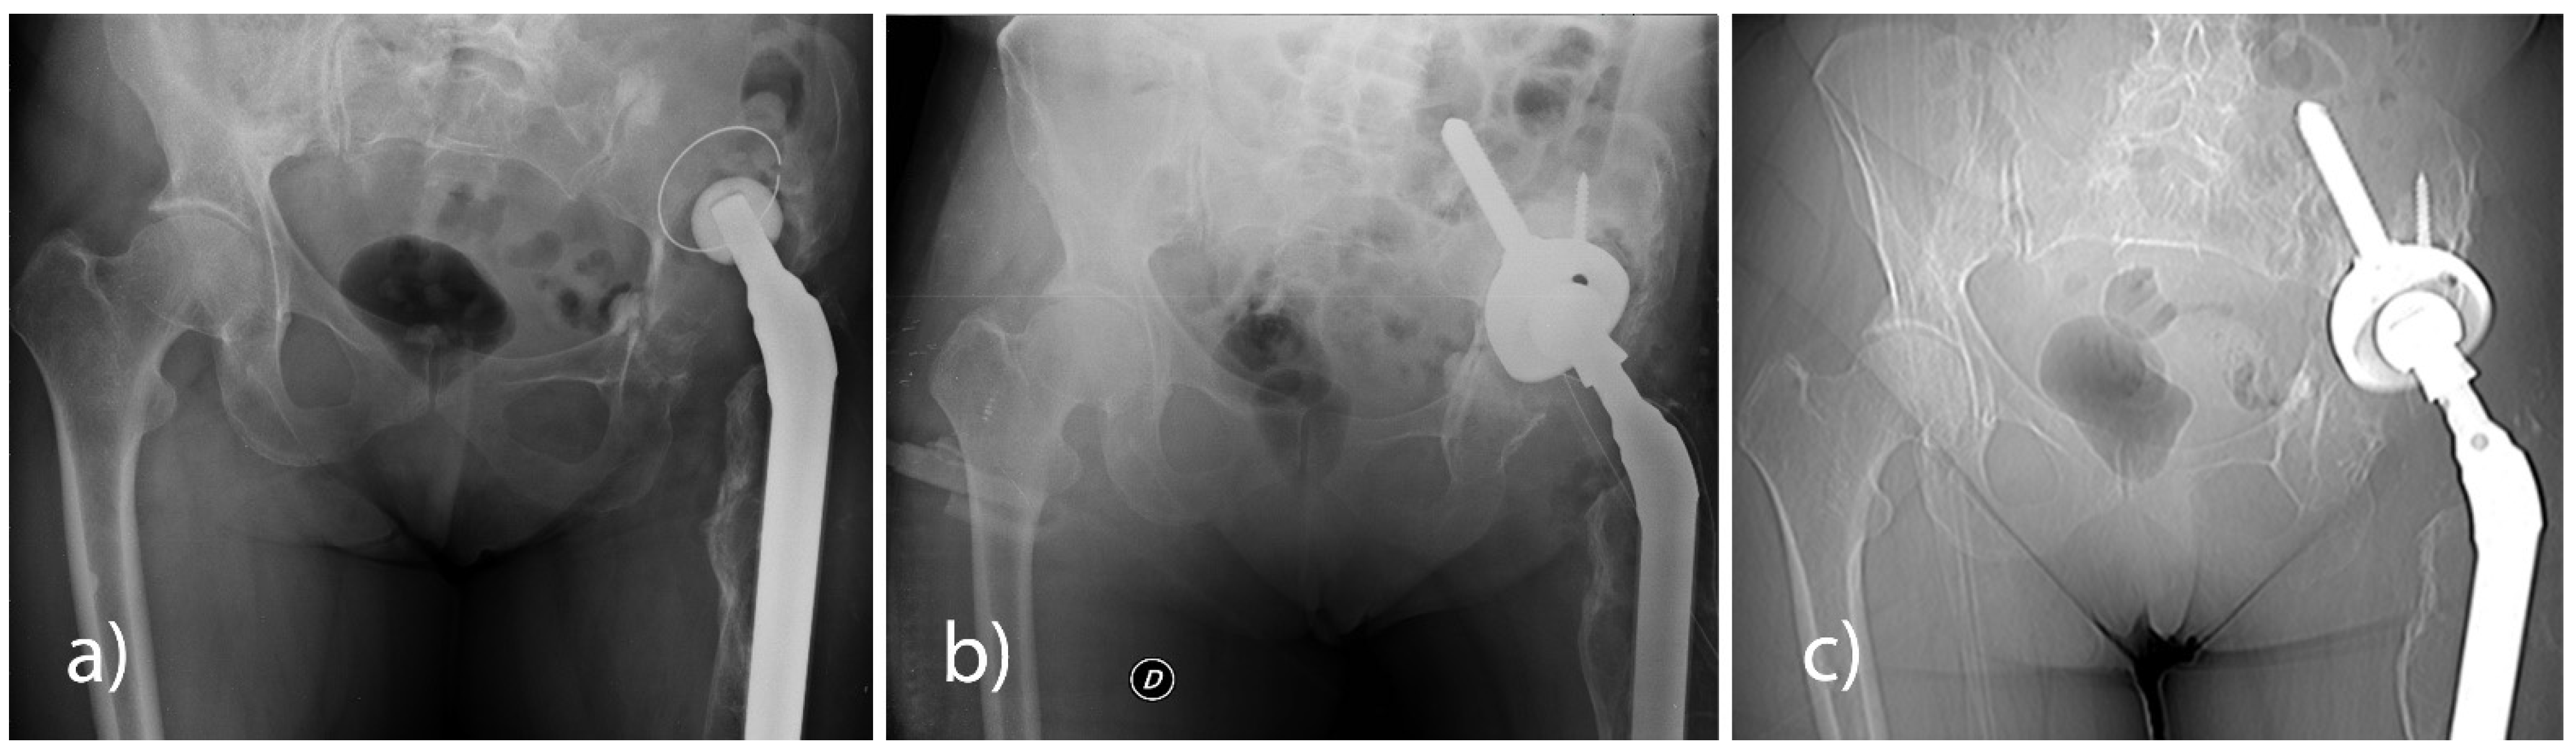

All patients underwent a pelvis X-ray check-up in AP projection in a standing position and with a lateral hip view at pre-hospitalisation and at 6, 12, and 24 months post-surgery. None of the patients had any signs of loosening of the implanted cup (Figure 1).

Figure 1. (a) Aseptic mobilization of the right hip prosthesis cup. (b) 6-month post-operative radiographic control shows the revised cup (Sansone cup with an iliac stem and RegenOss) stably in place. (c) A 12-month CT scan shows no signs of prosthetic loosening.